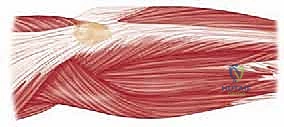

Reconstructable Radial Head Fractures

- Exposure: Through the extended posterior approach (Boyd modification), we gain direct visualization of the radial head fracture.

- Reduction: Using small-pointed reduction clamps or K-wire joysticks, meticulously reduce the fracture fragments. The goal is an anatomic reduction of the articular surface.

- Provisional Fixation: Secure the reduced fragments with 0.045" or 0.062" K-wires.

- Definitive Fixation: Apply minifragment screws (e.g., 2.0mm or 2.4mm) or specialized radial head plates. Ensure all hardware is countersunk and does not impinge on the capitellum or ulna during forearm rotation and elbow flexion/extension.

TECH FIG 2 • A,B. Preoperative and postoperative radiographs demonstrating open reduction and internal fixation of the radial head component of the Monteggia fracture.

* Pearl: After fixation, gently range the elbow and forearm through a full arc of motion to confirm stable fixation and absence of impingement. Use fluoroscopy to confirm concentric reduction of the radial head within the capitellum.